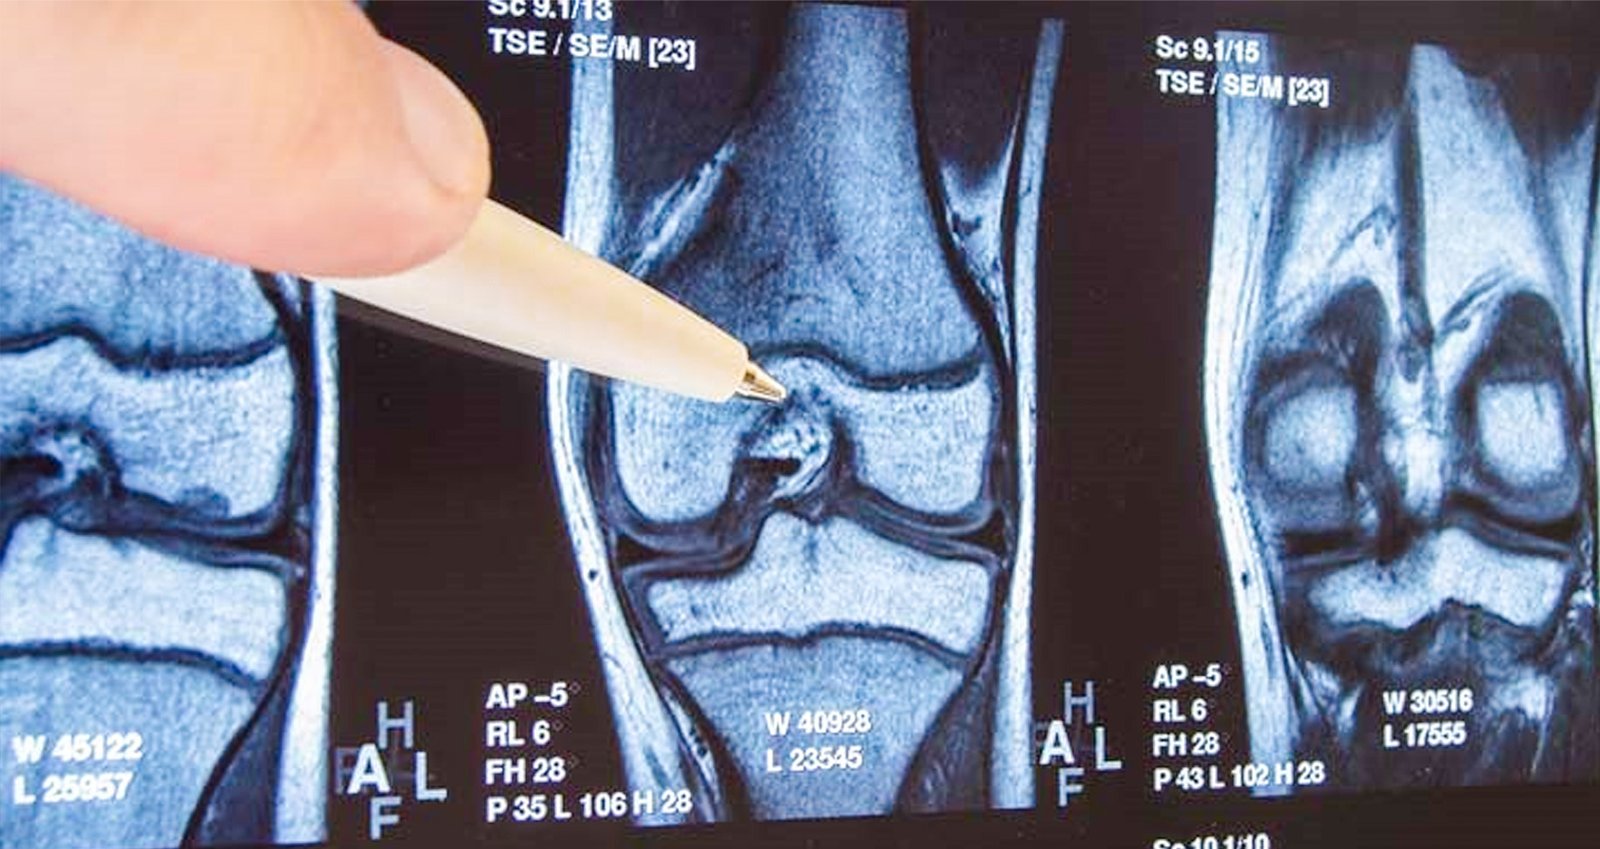

Knee osteoarthritis (OA) is becoming increasingly prevalent among the working-age population. The number of total knee replacements (TKRs) performed on individuals under 68 years old has risen significantly, with a 188% increase observed between 2000 and 2015 (AAOS, 2014). This trend is attributed to rising obesity rates, sedentary lifestyles, an ageing workforce, and increased physical demands in certain occupations.

While TKR is often an effective treatment for severe knee OA, it presents unique challenges for some younger patients:

1. Approximately 20% of TKR patients report dissatisfaction with the outcome, with younger patients more likely to experience ongoing pain and stiffness (Bourne et al., 2010).

2. The average lifespan of a knee implant is about 15-20 years, potentially less for those in physically demanding jobs (Kurtz et al., 2007).

3. Research indicates that TKR performed under age 55 often leads to poorer satisfaction and outcomes (Parvizi et al., 2014).

These factors underscore the importance of delaying surgery when possible and exploring alternative management strategies.